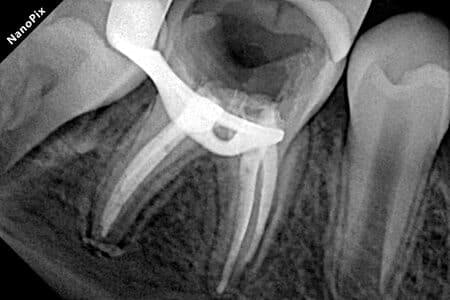

Детальніше...У Центрі Дитячої Стоматології лікаря Ковнацького ми віримо, що візит до стоматолога має бути для дитини не приводом для страху, а кроком до здорової та щасливої посмішки. Наша філософія базується на глибокому розумінні дитячої психології та фізіології, адже дитячі зуби потребують особливого підходу, а малюки – щирої турботи та довіри.